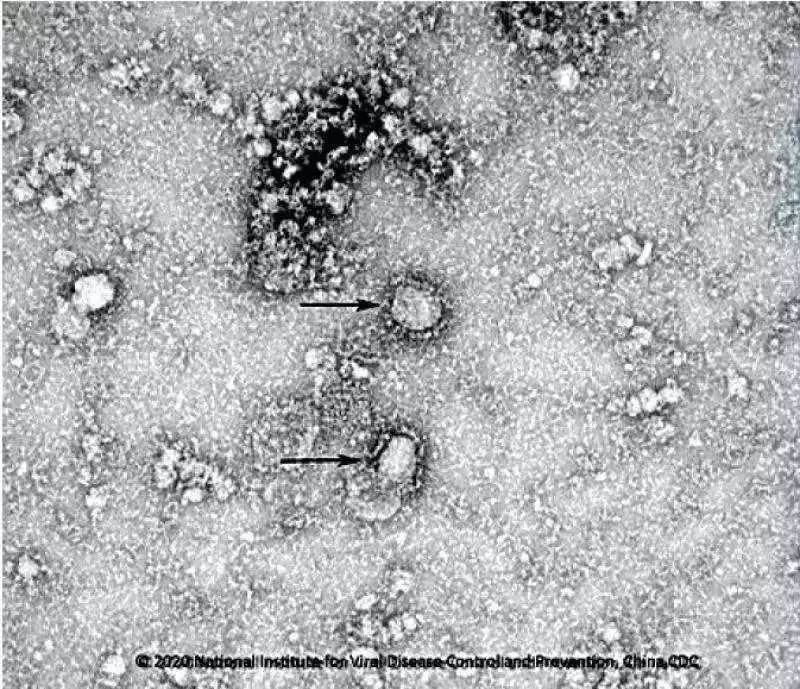

2. 国家病原微生物资源库于2020年1月24日发布了由中国疾病预防控制中心病毒病预防控制所成功分离的我国第一株病毒毒种信息及其电镜照片、新型冠状病毒核酸检测引物和探针序列等国内首次发布的重要权威信息,并提供共享服务